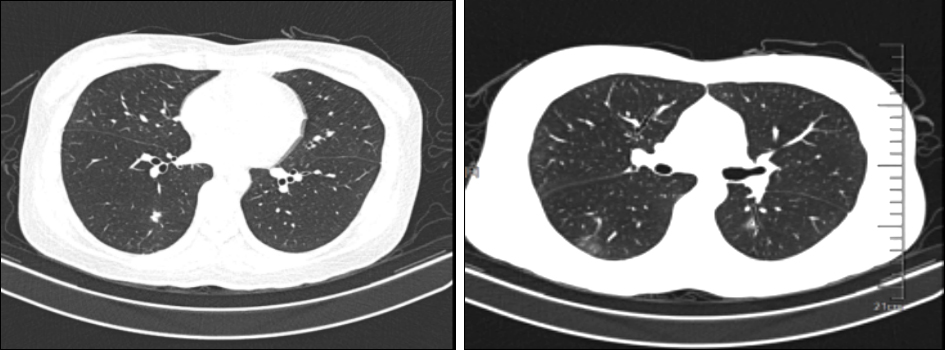

影像学检查

两肺可见散在小结节状、斑片状密度增高影及模糊影、少许条索影

影像学诊断:

1、两肺散在病灶,考虑炎症,嗜酸性粒细胞性肺炎?

2、双侧筛窦、左侧额窦及右侧上颌窦炎症。